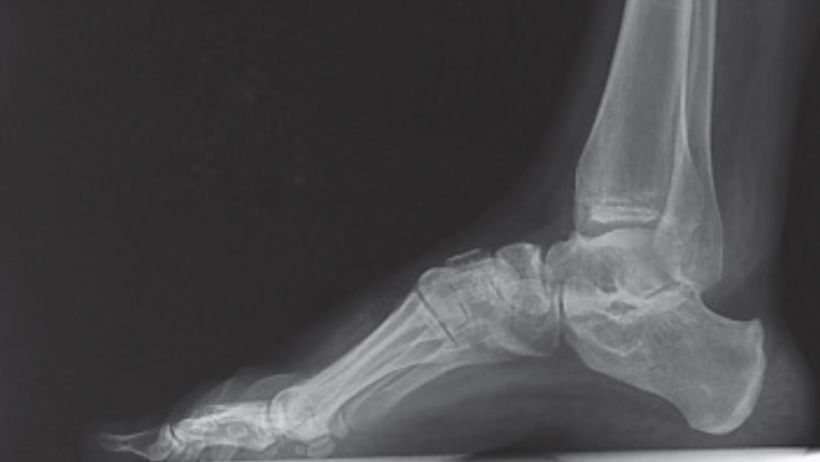

Sucede cuando hay una desviación de la primera cabeza metatarsiana sobre la segunda cabeza metatarsiana, y por eso se puede llamar Hallux Valgus.

Se da por varias causas, por ejemplo la artrosis, que puede ser causada por trauma; entre esos, el uso de zapatos estrechos o muy cortos, y también algunas enfermedades como la artritis, o la osteoporosis

Se presenta cuando se va perdiendo el líquido o el cartílago entre la cabeza del metatarso y la primera falange. Al perder movilidad, la articulación duele. También puede aparecer por traumas en deportistas que hacen cargas que afectan esa articulación. Para este tipo de juanete existen plantillas especiales, llamadas plantillas para Hallux Rigidus.